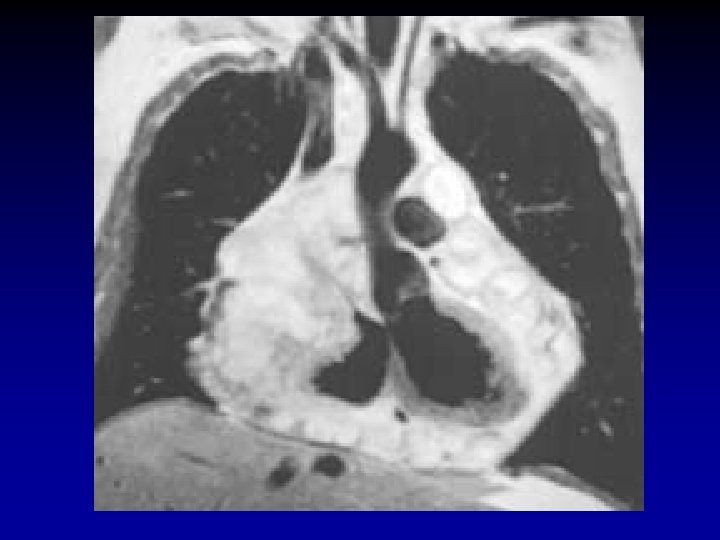

LABORATORIO DIAGNÓSTICO RM • Información morfológica detallada • Excelente correlación con patología • Útil en detección de lipomas • Información sobre vascularización del tumor • Valoración de cavidades, pericardio y estructuras adyacentes • Información tridimensional

TUMORES BENIGNOS MIXOMA AURICULAR • Rx • 50% tienen AI grande y signos de HTP • 30% Rx normales • Ecocardiografía • Diagnóstico • Identificar sitio de unión del tumor • Descartar compromiso valvular • Descartar masas múltiples • Planear cirugía • Control Pos. Qx